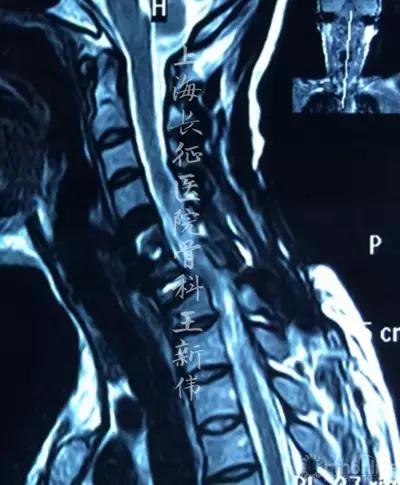

颈椎MRI平扫:

第二次术前颈椎MRI平扫,可见C6/7存在成角畸形,脊髓受压

考虑到患者C7存在骨折楔形变,C6/7术后仍存在关节突绞锁,椎间成角畸形,脊髓受压,再次手术解除脊髓成角畸形,解除后方小关节绞锁,改善SVA等等均是手术亟待解决的目标。